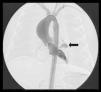

Paciente varón de 7 días de vida, al que se diagnostica de estenosis valvular aórtica severa, y se decide realización de valvuloplastia aórtica percutánea mediante abordaje retrógrado con catéter pig-tail por vía transaórtica. Se aprecia fractura de catéter dentro del ventrículo izquierdo, tras recambio del mismo se realizan inyecciones en ventrículo izquierdo, en las que se aprecia una imagen de fuga en pared antero-lateral del mismo limitada a la zona subepicárdica (fig. 1), correspondiente a pseudoaneurisma de boca muy estrecha. Se continua el procedimiento para disminuir la presión en ventrículo izquierdo, realizando la valvuloplastia percutánea (relación balón-anillo aórtico=0,9), con buen resultado. Se comenta con cirugía cardiaca y se decide mantener en observación, con controles ecocardiográficos frecuentes (Imagen 2). A los 2 días del procedimiento, presenta taponamiento cardiaco que requiere pericardiocentesis urgente y traslado del paciente a quirófano, donde se visualiza hemopericardio a tensión y hematoma intramiocárdico con zona disrupción amplia central, realizando sutura continua doble. No incidencias tras la cirugía. En los controles posteriores ha permanecido estable y libre de intervención.

Ventriculografía izquierda en sístole ventricular antero-posterior en la que se aprecia un pseudoaneurisma (contenido por pericardio visceral) en la cara lateral del ventrículo izquierdo. Así mismo se aprecia apertura aórtica en cúpula con ambos velos engrosados y dilatación de aorta ascendente.